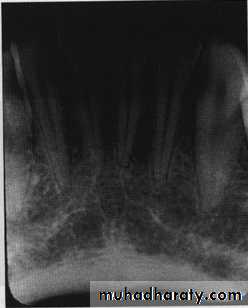

Carcinoma erosion of alveolar crest & ill defined borders.

Blending border into adjacent area –gradual transition-normalappearing bone & abnormal appearing trabeculae -sclerosing osteitis• Invasive irregular border-bone destruction-malignancy.

Invasive irregular border-bone destruction/SCC